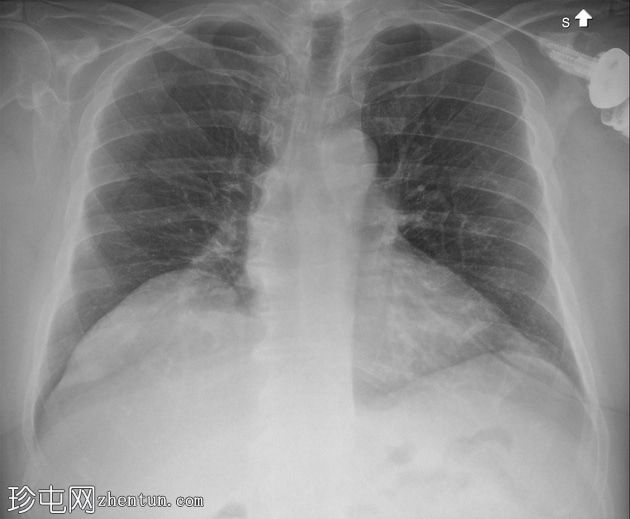

正面 - 外旋

全肩关节置换术后肱骨假体前脱位,伴假体分离。